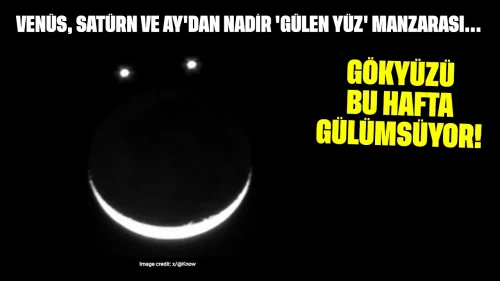

Yumurtalık zayıflığı, tıbbi adıyla primer over yetmezliği, yumurtalıkların yeterli düzeyde yumurta üretememesi ya da yumurtlama döngüsünü sağlıklı bir şekilde sürdürememesi durumudur. Bu durum, kadınların hormonal dengelerini de etkileyerek östrojen seviyelerinin düşmesine yol açabilir. Yumurtalık zayıflığı, menopozdan farklıdır çünkü bu durumdaki kadınlar hala düzensiz de olsa adet görebilir ve nadiren de olsa doğal yolla hamile kalabilir.

Yumurtalık Zayıflığının Nedenleri

Yumurtalık zayıflığının altında yatan birçok neden olabilir. Bunlar arasında genetik, çevresel ve yaşam tarzı faktörleri yer alır:

- Genetik Faktörler

Turner sendromu gibi kromozomal anormallikler. Ailede erken menopoz öyküsü. - Otoimmün Hastalıklar

Vücut, yumurtalık dokusunu yanlışlıkla hedef alabilir. - Kemoterapi ve Radyoterapi

Kanser tedavisinde kullanılan yöntemler, yumurtalık hücrelerine zarar verebilir. - Enfeksiyonlar

Bazı enfeksiyonlar, yumurtalık fonksiyonlarını olumsuz etkileyebilir. - Yaşam Tarzı Faktörleri

Sigara kullanımı ve obezite gibi alışkanlıklar yumurtalık sağlığını olumsuz etkileyebilir.